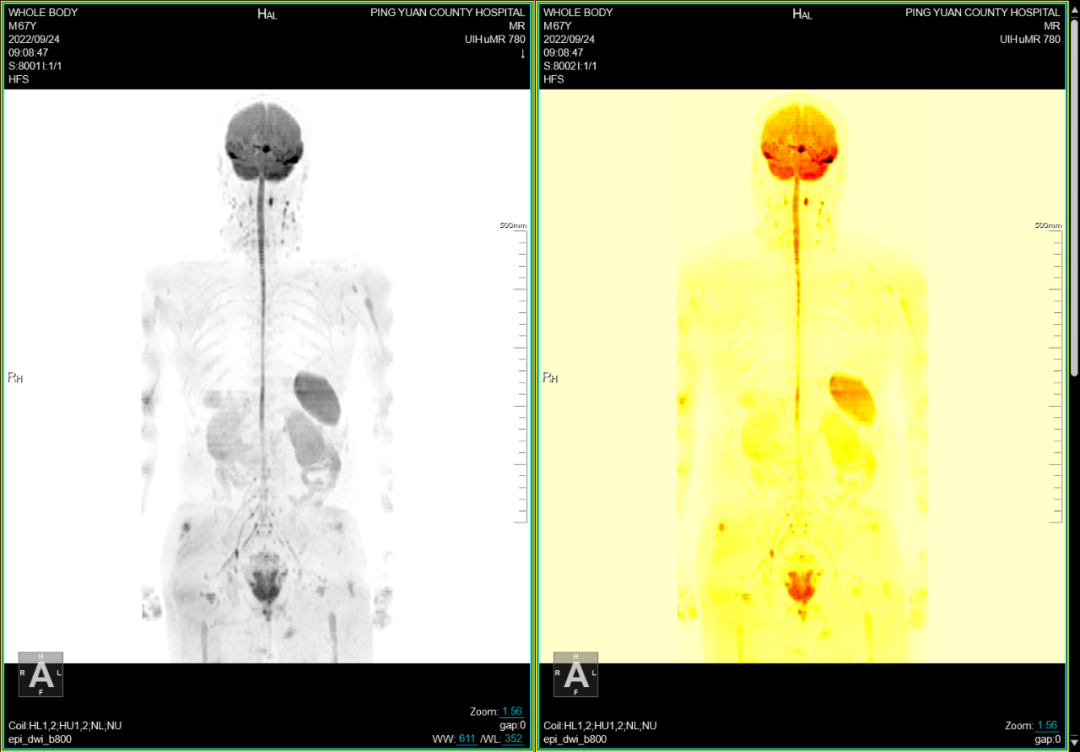

七、全身类PET成像,此项检查技术主要用于全身转移肿瘤的筛查:

①磁共振类 PET成像对全身恶性肿瘤病变性质的诊断,尤其对全身转移灶的筛查,淋巴结转移筛查及恶性肿瘤的分期评估具有很高的价值。②对已明确发现转移性病灶寻找其原发灶;术后放化疗的效应观察等具有较大优势。③对高危人群的肿瘤筛查具有实用价值。

联影磁共振怎么样平原县第一人民医院联影uMR780 光梭3.0T磁共振正式投入使用,开启医学影像新时代!_https://www.jmylbn.com_新闻资讯_第17张

联影磁共振怎么样平原县第一人民医院联影uMR780 光梭3.0T磁共振正式投入使用,开启医学影像新时代!_https://www.jmylbn.com_新闻资讯_第18张

联影磁共振怎么样平原县第一人民医院联影uMR780 光梭3.0T磁共振正式投入使用,开启医学影像新时代!_https://www.jmylbn.com_新闻资讯_第19张

联影磁共振怎么样平原县第一人民医院联影uMR780 光梭3.0T磁共振正式投入使用,开启医学影像新时代!_https://www.jmylbn.com_新闻资讯_第20张

联影磁共振怎么样平原县第一人民医院联影uMR780 光梭3.0T磁共振正式投入使用,开启医学影像新时代!_https://www.jmylbn.com_新闻资讯_第21张

联影磁共振怎么样平原县第一人民医院联影uMR780 光梭3.0T磁共振正式投入使用,开启医学影像新时代!_https://www.jmylbn.com_新闻资讯_第22张

联影磁共振怎么样平原县第一人民医院联影uMR780 光梭3.0T磁共振正式投入使用,开启医学影像新时代!_https://www.jmylbn.com_新闻资讯_第23张